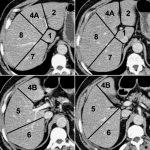

Giải Phẫu CT Bụng | Bài giảng CĐHA

Giải phẫu cắt lớp vi tính ổ bụng.

# Giải phẫu hạ phân thùy gan.